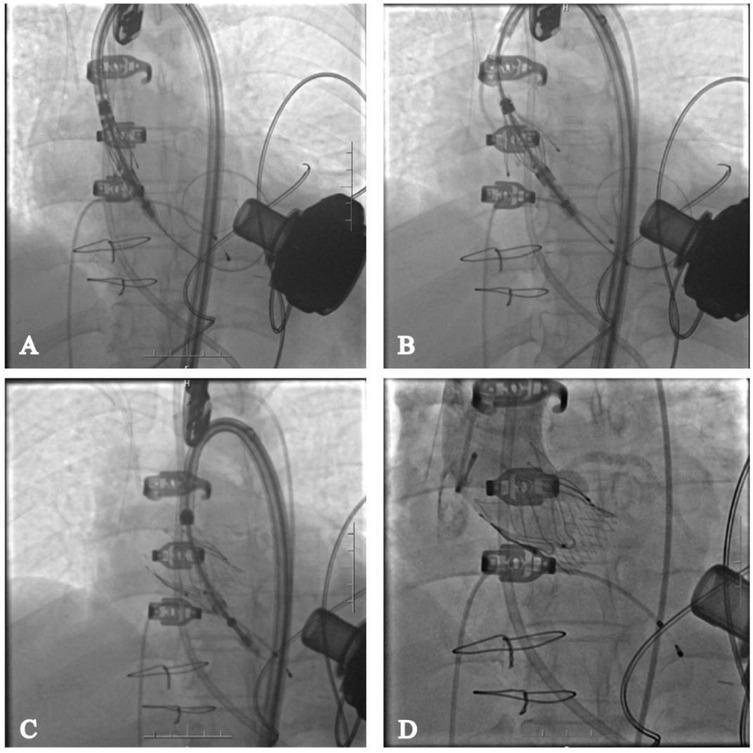

Surgical procedure

The procedure was successfully performed under general anesthesia in the hybrid operating room via the right femoral artery (Figure 3). LVAD pump speed was maintained at 2,250 rpm, consistent with the preoperative setting. A temporary pacing lead was placed through the left femoral vein, and the left femoral artery was used as secondary access. Under fluoroscopic and echocardiographic guidance, a Taurus Trio-THV 25 valve (28 mm) was implanted via the right femoral artery, with all three locators stably anchored at the sinus base. No rapid pacing was required, and the continuous-flow LVAD did not interfere with valve positioning or deployment. Post-deployment aortography demonstrated only trivial paravalvular leak with patent coronary arteries. Intraoperative transesophageal echocardiography confirmed optimal valve position and morphology, with no paravalvular leak and immediate resolution of aortic regurgitation (Figure 4). Given the patient's long-term warfarin therapy (INR 2–3) due to prior LVAD implantation, the main access site was closed with two ProGlide devices, achieving effective hemostasis, and ultrasound confirmed the absence of bleeding, dissection, or stenosis.

Figure 3

Transcatheter aortic valve replacement via femoral artery. (A) Deliver the valve to the annulus location; (B) deploy the proprietary locator into the sinus of valsalva; (C) release the valve; (D) angiography shows no regurgitation of the aortic valve and no impact on coronary perfusion.